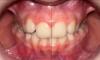

Девочки,сняли сегодня аппарат Марко Росса. Результат за пол года . Теперь весной брекеты ,либо элайнеры 2*4,либо ждем смены Зубов и ставим полноценные на весь рот ,будет понятно после КТ в феврале. Результатом на данный момент мы очень довольны 👍 фото в коментах) первые фото ДО,рядом после.